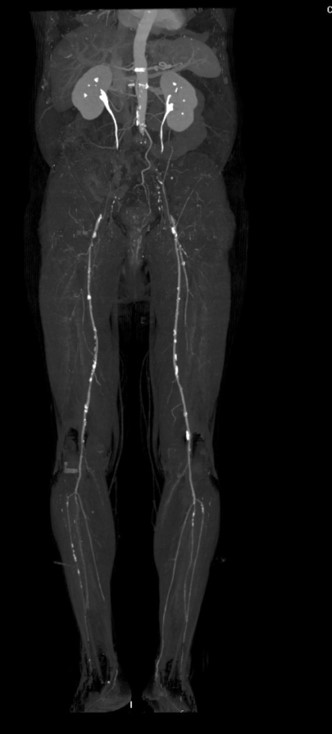

•МСКТ аорты и артерий н/конечностей: КТ признаки окклюзии терминального отдела аорты и подвздошных артерий с обеих сторон.

Пациент Ч.  МСКТ